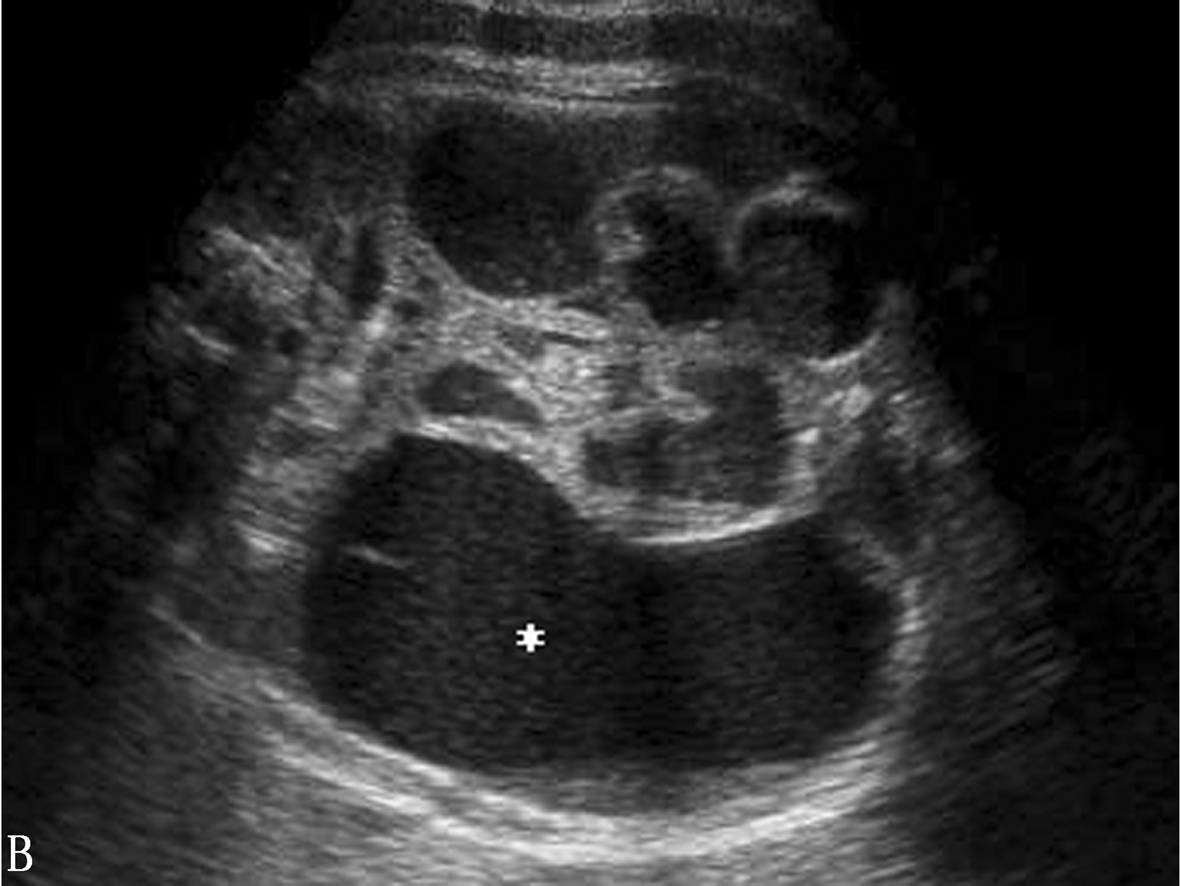

图2 孕29周胎儿直肠肛门闭锁致肠管全程扩张

产前超声的重要表现是结肠扩张(图1,2)。大肠直径随着孕周的增大而增大,因此,判断结肠是否扩张,应根据检查时的孕周来判断。正常胎儿结肠直径在25周时不超过7mm,足月时不超过18mm。肛门闭锁时,常在胎儿盆腔下部显示出“V”形或“U”形扩张的肠管;结肠腔内可见到钙化,提示可能有肠结石,可能由胎粪浓缩和凝固而成的。未检出肠管扩张不能除外肛门闭锁的可能。产前超声诊断缺乏特异性。早孕期检出肠道扩张可能为肛门闭锁的一个标志。

图1 孕14周胎儿肛门闭锁,盆腔下部肠管扩张呈“双叶”征